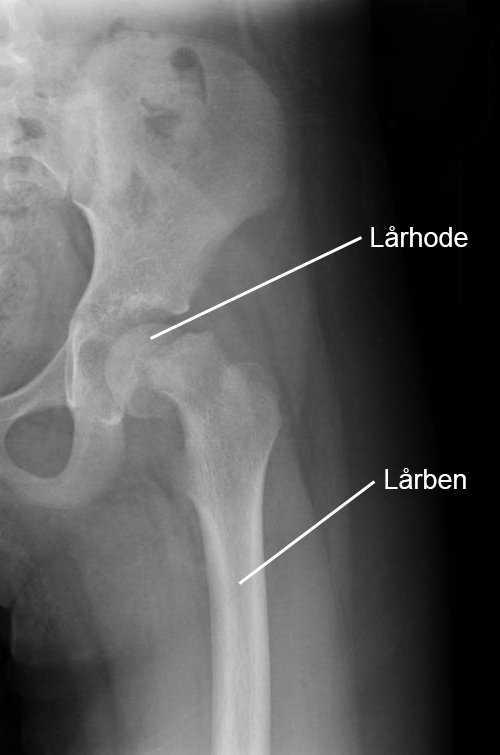

Diagnosen stilles basert på pasientens historie og en fysikalsk undersøkelse, der det viser seg at bevegeligheten i hoften er nedsatt og smertefull. For å bekrefte diagnosen tas det røntgenbilder, hvor en avglidning av lårbeinshodet (ved epifysiolysis capitis femoris) kan observeres.